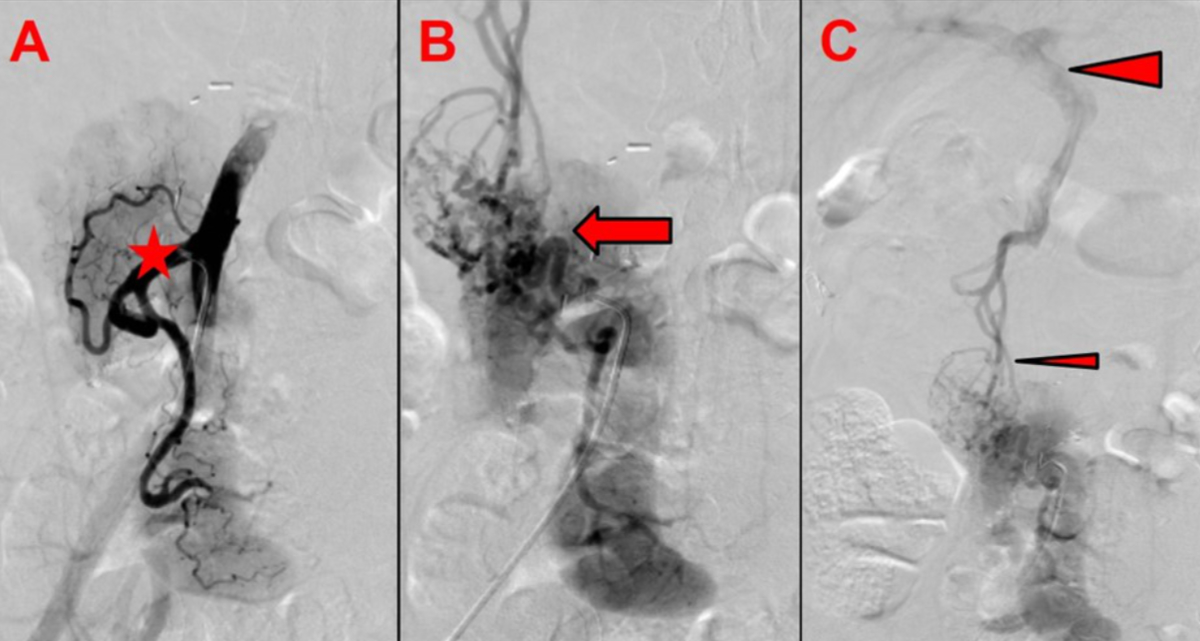

Almost 2.5 years after transplantation, the patient suffered from lower gastrointestinal bleeding. An upper endoscopy showed evidence for variceal bleeding at the level of the graft-duodenal anastomosis. Subsequent angiography revealed an unusual finding of a complete thrombosis of the graft portal vein, with preserved venous outflow via newly formed varicose veins draining into the patient’s own portal venous system (figure 4). Pancreatic graft function remained excellent, with persistent insulin freedom and normal HbA1c. An interdisciplinary panel opted against attempting an interventional venous recanalisation, due to the high risk of complications. The option of a preventive graft removal to exclude the risk of variceal bleeding was considered disproportionately risky and refused by the patient. Within the six months after diagnosis, no further episodes of gastrointestinal bleeding occurred under persistent graft function.

Figure 4Pancreas graft venous outflow. (A) Arterial angiography shows homogeneous arterial perfusion of the pancreas graft with open arterial anastomosis (asterisk: arterial Y-graft). (B) Venous angiography shows no venous outflow via the graft portal vein and vena cava (arrow: gross variceal formations are visible around the graft pancreas head and duodenum). (C) Venous outflow via variceal formation draining into the patient’s own portal vein (small arrowhead: varicose veins around the graft pancreas head and duodenum; large arrowhead: patient’s portal vein).